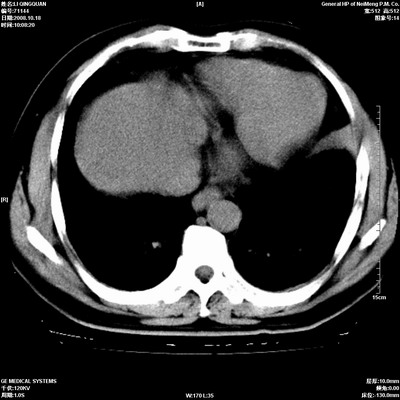

以下是引用duguo在2008-10-19 13:59:00的发言:[br]左肺上叶支气管狭窄,首先考虑中心型肺癌伴阻塞性肺炎\\肺不张.

以下是引用ybing在2008-10-19 12:58:00的发言:[br]左肺上叶阻塞性炎症-建议支气管镜进一步检查除外中央型肺癌

以下是引用随光逐影在2008-10-19 14:31:00的发言:[br]考虑左肺中央型肺癌并左肺上叶阻塞性肺炎,肺不张。